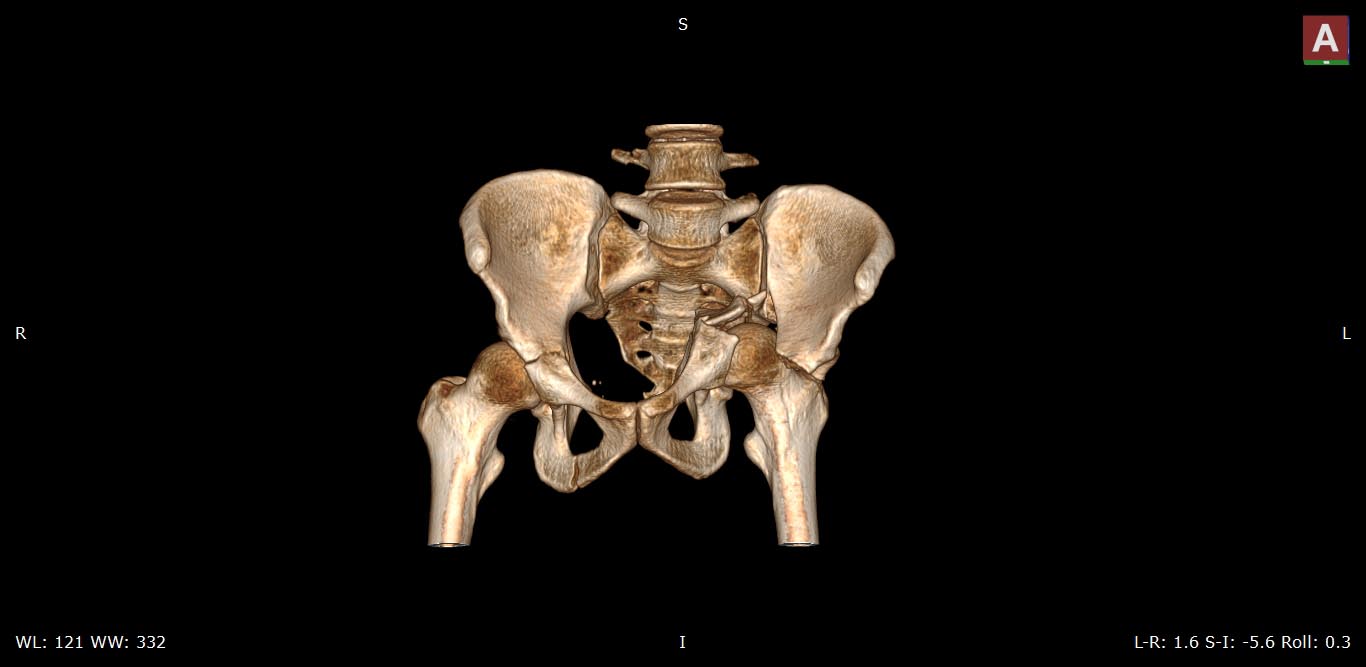

Это поперечный перелом вертлужной впадины, а не перелом таза.

И справа похоже тоже вертлужка сломанна .

Да, справа без смещения

Добрый день, уважаемые коллеги! Данный случай-полифокальное повреждение таза.Самый неблагоприятный вариант поперечно ориентированного перелома вертлужной впадины и ротационно нестабильное повреждение тазового кольца (КПС). Оперативное лечение- открытая реконструкция сустава и перкутанная фиксация КПС.

Вчера (17.10.17) снимок на месте палатным аппаратом.

Положение отломков прежнее.

Кт в день поступления прилагаю.